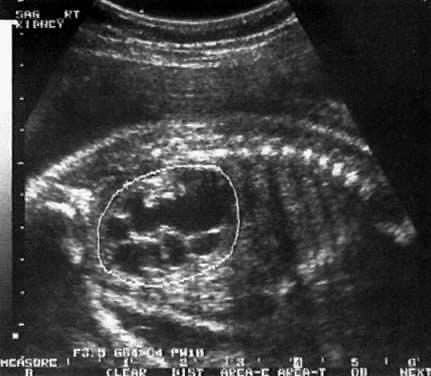

Tanı hekimin yapacağı fizik muayene ile konur. Prepüsyumun kısmi veya tam geri çekilememesinin yanı sıra sünnet derisinin iç yüzeyi ile penisin baş kısmı arasında yapışıklıklar görülür.